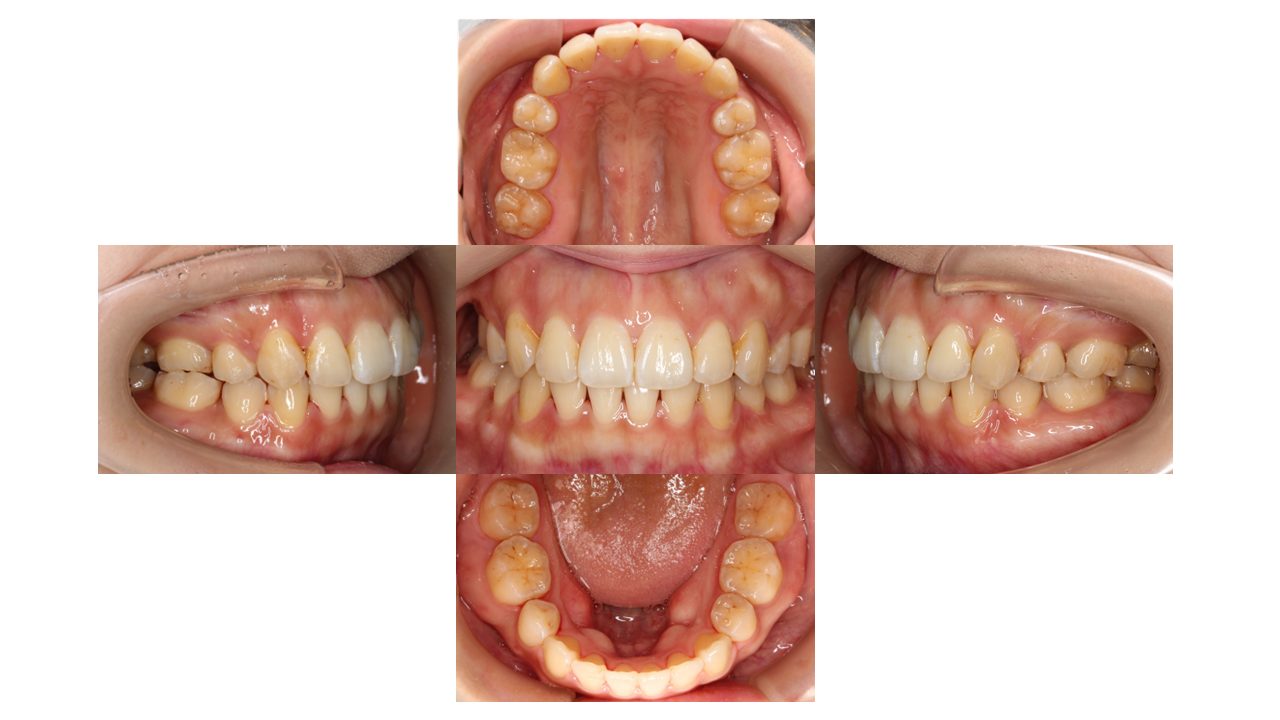

初診時の口腔内の状態です。

前歯の凸凹・口元が出ていることがお悩みでご来院されました。